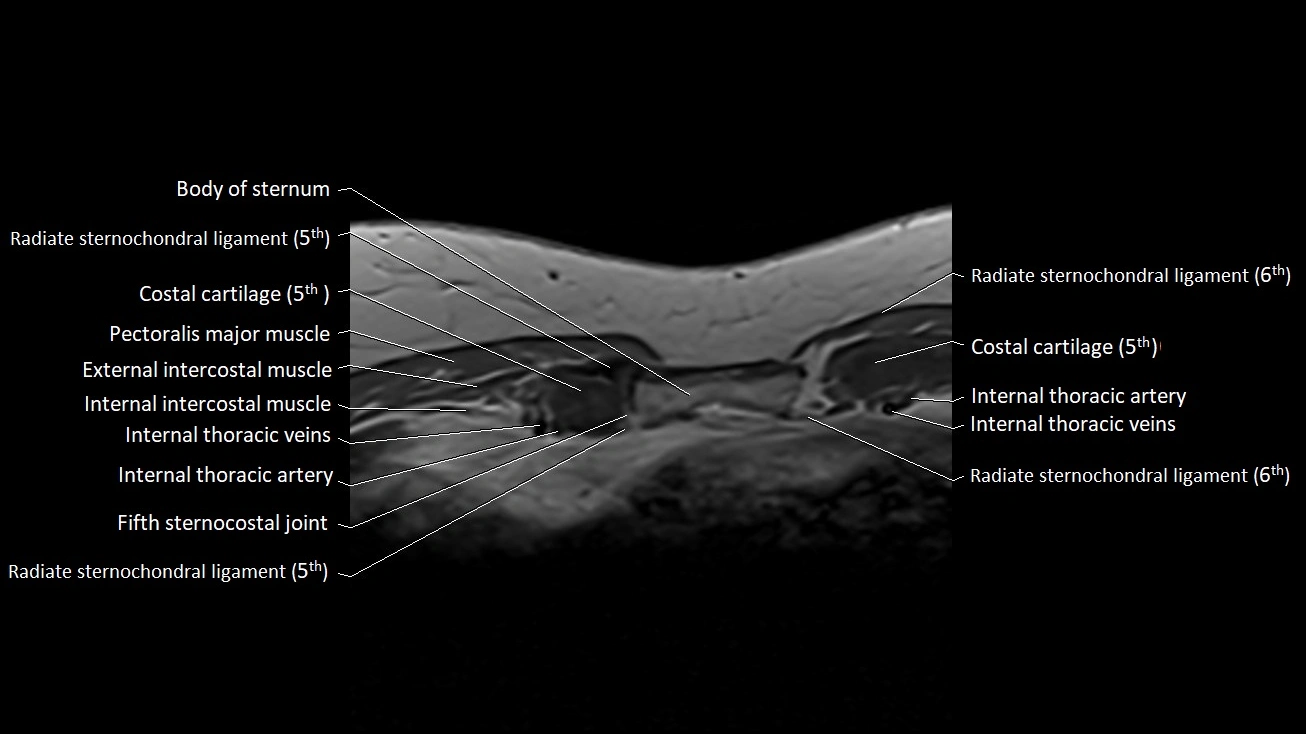

MRI images

image